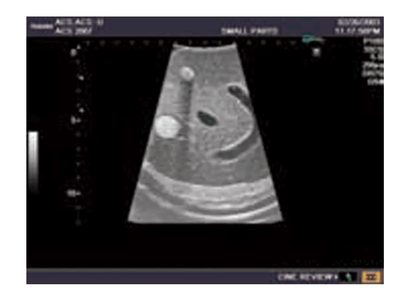

Das Ultraschall-Modell für Sonografie ist speziell für die Ausbildung von Anfängern und die Demonstration durch Fachleute konzipiert. Es bietet eine detaillierte und realistische Darstellung der Anatomie des Abdomens, einschließlich der Leber, Gallenwege, des Pankreas und der Nieren. Das Modell erfüllt die höchsten Anforderungen an eine exzellente Ausbildung und ermöglicht die Durchführung von offenen intraoperativen Sonografien sowie laparoskopischen Untersuchungen, um etwaige Läsionen und Steinbildungen zu prüfen. Es umfasst eine Vielzahl von Läsionen wie Gallensteine, Zysten und Tumore, die in den verschiedenen Organen simuliert sind, um realistische Übungsmöglichkeiten zu bieten.

Simulierte Läsionen (solide Tumore, Zysten, Gallensteine) in wichtigen Organen für praxisnahe Ausbildung

Integrierte Simulation von organischen Läsionen und Tumoren, die in die Organe eindringen, für die Übung und Diagnostik

Modell enthält eine detailgetreue Darstellung von Gefäßstrukturen wie Aorta, Vena cava, Vena portae und Nierengefäßen

Die Simulation von pathologischen Befunden wie Tumoren, Zysten und Steinbildungen ermöglicht eine umfassende Vorbereitung auf die Ultraschalldiagnostik